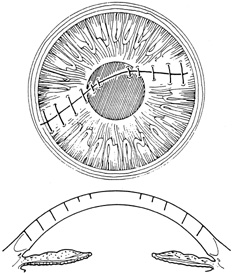

Cyanoacrylate tissue adhesive has been successfully used by ophthalmologists for many years despite not being approved by the U.S. Food and Drug Administration. Tissue adhesive is particularly useful for puncture wounds with small amounts of central tissue loss and selected small lacerations.4

Tissue adhesive should be applied to a dry, deepithelialized bed. A capillary microapplicator or fine-gauge disposable needle is used to apply a very thin film of adhesive over the site (Fig. 3). Alternatively, adhesive may be applied using a sterile 2- to 4-mm polyethylene or silicone disc affixed to the end of an applicator stick with sterile ophthalmic ointment. The disc may be left in place or removed with care. Three to five minutes are required for polymerization of the adhesive. A bandage soft contact lens is applied for comfort and to prevent the glue from dislodging. While the contact lens is in place, a prophylactic antibiotic drop is administered. Over time, the tissue adhesive dislodges spontaneously as the wound surface reepithelializes. Alternatively, it may be gently removed with forceps after adequate stromal healing has occurred.